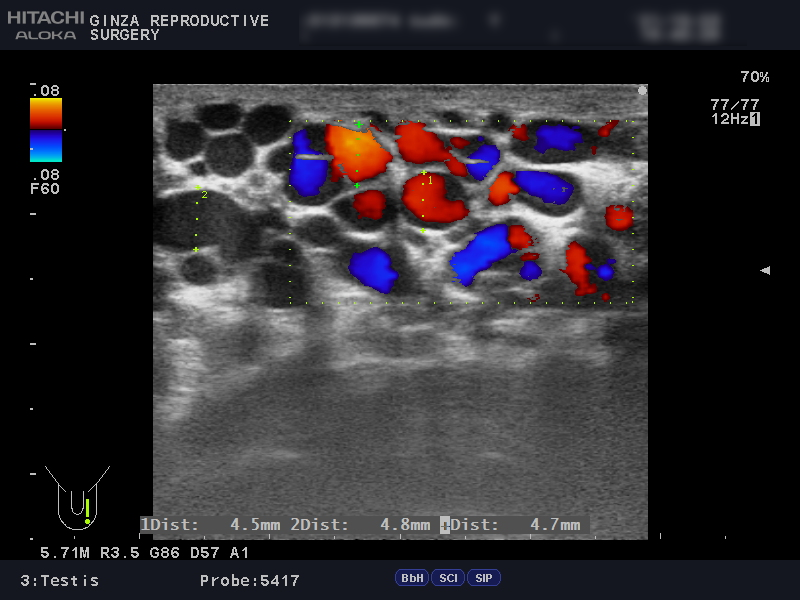

精索静脈瘤の診断には、エコー検査を用います。

エコー検査では、精巣内や精巣上体の観察と精索静脈瘤の診断を行います。同時に不妊や別の病気と関連している、以下のような異常がないかどうかも詳しく確認します。

以下は、当院でエコー検査を受けられた患者さんの画像です。

精索静脈径が3mm以上だと治療を推奨されるところ、左側の画像では4.5~6.8mmで、血管が明らかに拡張しています。

安静にしていてもドップラー法で顕著な逆流が観察でき、腹圧でさらに増強していました。ドップラー法は、血液の逆流を確認する方法です。

上の画像検査結果より、グレード3の左精索静脈瘤であると診断されました。